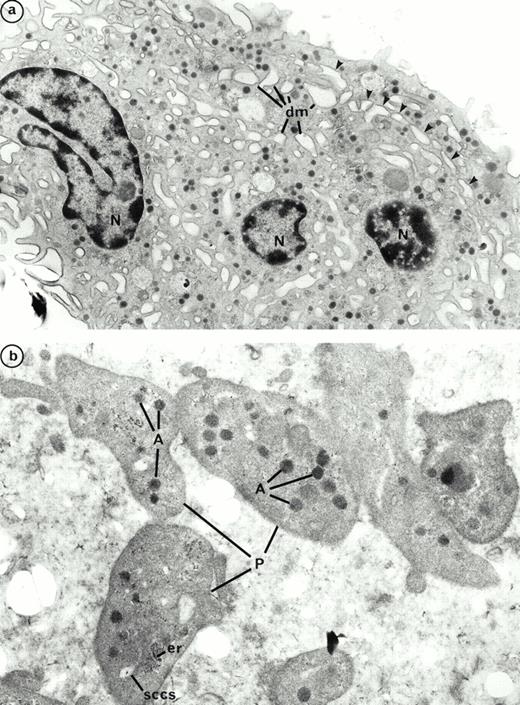

We previously described the ultrastructure of platelet formation by human MKs cultured with PEG-rHuMGDF.29 No substantial differences were observed in the ultrastructure of the platelet-shedding MKs produced in the presence of either PEG-rHuMGDF or the combination of IL-3, SCF, and IL-6. In the two conditions, platelet shedding MKs showed several cytoplasmic expansions which correspond to proplatelets (Figs 9a and10a); constriction zones already individualize distinct platelet fields. In the same way, platelets derived from culture with either PEG-rHuMGDF or the combination of IL-3, IL-6, and SCF were of similar size and exhibited α- and dense granules. Many of these platelets were adherent to MKs; however, they did not exhibit ultrastructural evidence of activation (Figs 9b and 10b). By fluorescent labeling, circumferential microtubule coils and actin filaments were observed with an antitubulin MoAb and phalloidin in the vast majority of the culture-derived platelets (data not shown).

Ultrastructure of platelet shedding MKs and platelets obtained in the presence of PEG-rHuMGDF from CD34+CD41+ cells. (a) A mature MK presenting signs of platelet formation. This MK displays dilatation of the demarcation membranes (dm) located at the periphery. They individualize a zone of cytoplasm (arrows) which will form a future proplatelet (N, nucleus). (b) Platelet-sized-fragments (P) exhibit the usual cytoplasmic organelles: α granules (A), smooth connected canalicular system (sccs), and endoplasmic reticulum (er).

Ultrastructure of platelet shedding MKs and platelets obtained in the presence of the combination of SCF, IL-3, and IL-6 from CD34+ CD41+ cells. (a) A similar mature MK as in Fig 9a with dilatation of demarcation membranes (dm) at the periphery (arrows) (N, nucleus). (b) Platelet-sized-fragments (P) are present with the combination of three cytokines. They are similar to those obtained with PEG-rHuMGDF (Fig 9b). On a proplatelet (PP), a constriction zone area is disposed along the cytoplasmic extension individualizing a distinct platelet field with a vacuole at the level of the future rupture (arrow) (A, α granules; sccs, smooth connected canalicular system; er, endoplasmic reticulum).